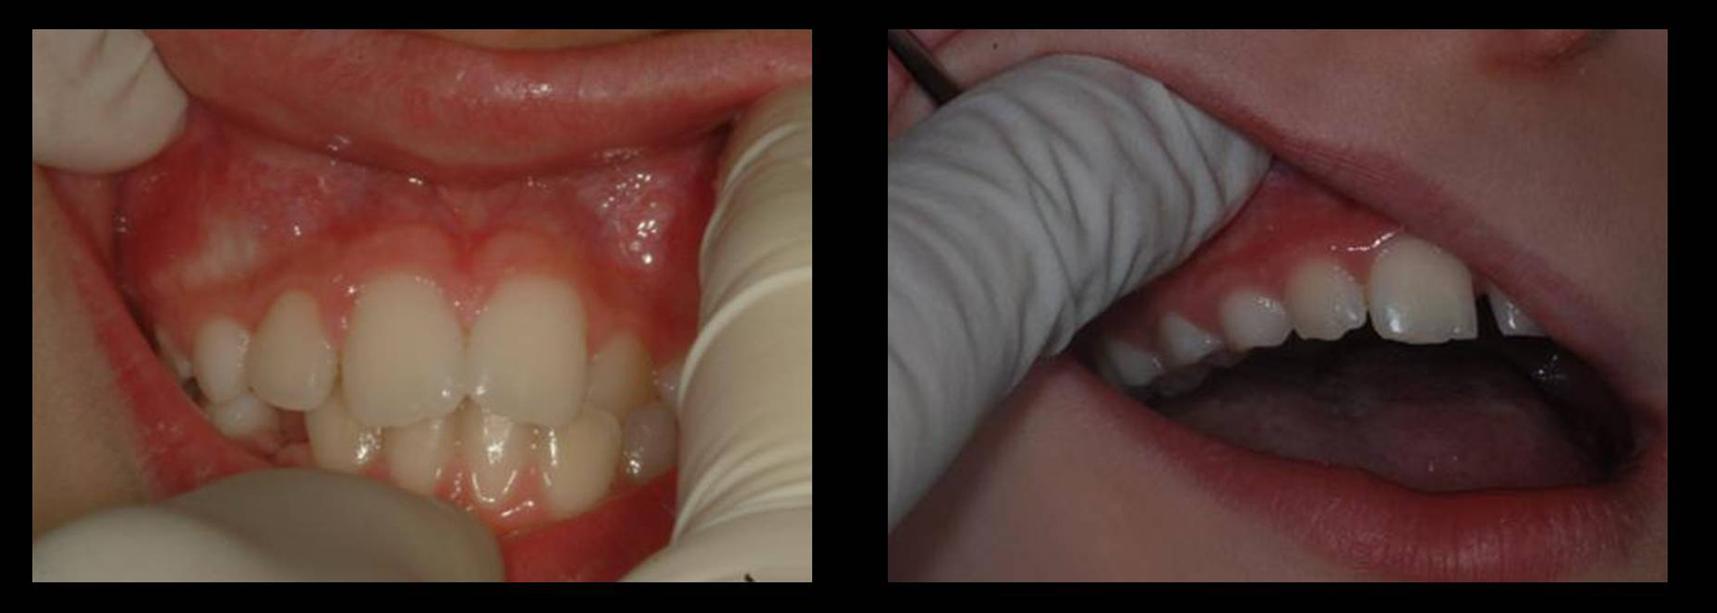

Sono indicatori di rischio clinici: 1) l�assenza della bozza canina o l�identificazione della stessa in sede ectopica (Figura 2-a); 2) l�anomala inclinazione e/o rotazione di uno o entrambi gli incisivi laterali mascellari (Figura 3-b); 3) la persistenza del canino deciduo oltre i normali limiti della permuta, specie se monolaterale (Figura 2-c).

L�ispezione e la palpazione del fornice vestibolare, eseguita annualmente a partire dagli 8 anni di et�, costituisce parte integrante della visita ortodontica (Figura 3). L�identificazione della bozza canina in sede vestibolare e apicale al canino deciduo � indicativa di una posizione corretta del canino permanente in eruzione2. Se un canino � palpabile in una posizione anomala o addirittura non � avvertibile alla palpazione, si rende indispensabile un�indagine radiografica per la sua localizzazione (Figura 2-a).

3. Ispezione e palpazione del fornice vestibolare.

L'identificazione della bozza canina in sede vestibolare � importante per la valutazione della posizione intraossea del canino permanente in eruzione.

La posizione della corona dell�incisivo laterale adiacente pu� essere influenzata dalla localizzazione intraossea del canino permanente per il loro reciproco rapporto di contiguit� anatomica1,2. Una sua attenta valutazione � quindi fondamentale nella diagnosi clinica di ectopia del canino (Figura 2-b).